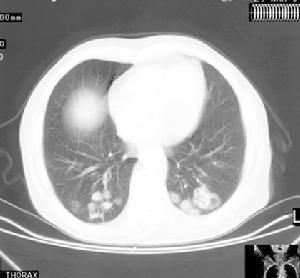

Wegner肉芽腫是系統性血管炎的一組症候群還沒有一種滿意的診斷和分類方法1990年美國風濕病學會根據一項分析研究結果制定了一套診斷標準。該研究共收集了85例Wegner肉芽腫及722例其他形式的血管炎作為對照組。該標準主要有4項,診斷Wegner肉芽腫的敏感性為88%特異性為92%如果血管炎患者具有下述4項標準中的2項或2項以上就可診斷為Wegner肉芽腫:①鼻或口腔炎症;②胸部X線片異常;③尿沉澱異常;④活檢結果為肉芽腫性炎症鑑別Wegner肉芽腫和其他血管炎病的最佳指標是活檢呈現肉芽腫性炎症改變。然而這一診斷標準在套用中也存在一定的缺陷,因為在實驗組中有近12%的Wegner肉芽腫患者並未被診斷出此病(即假陰性)該項研究的最大缺點是在其診斷標準中沒有設立抗中性粒細胞胞漿自身抗體的相關內容,因為當時檢測此抗體的技術還未得到廣泛套用。

Wegener肉芽腫(韋格納肉芽腫病,WegenerGranulomatosis,WG)是一種病因不明的血管性、系統性、炎症性疾病,臨床表現以呼吸道壞死性肉芽腫性炎症,局灶性壞死性腎小球腎炎和累及其它周身器官的血管炎為主要特徵。本病發病率較低,屬於非常見病,易誤診和漏診。Wegener肉芽腫年發病率為百萬分之0.5到8.5。另外8%~16%的Wegener肉芽腫患者以眼部為首發症狀,28%~87%的患者最終累及眼部。眼部表現可為鄰接型和灶型兩種。眼部表現包括嚴重眼眶假瘤,眼眶膿腫、蜂窩組織炎或者鼻淚管阻塞,其中眼眶炎症伴眼球突出是Wegener肉芽腫最常見的眼部表現。